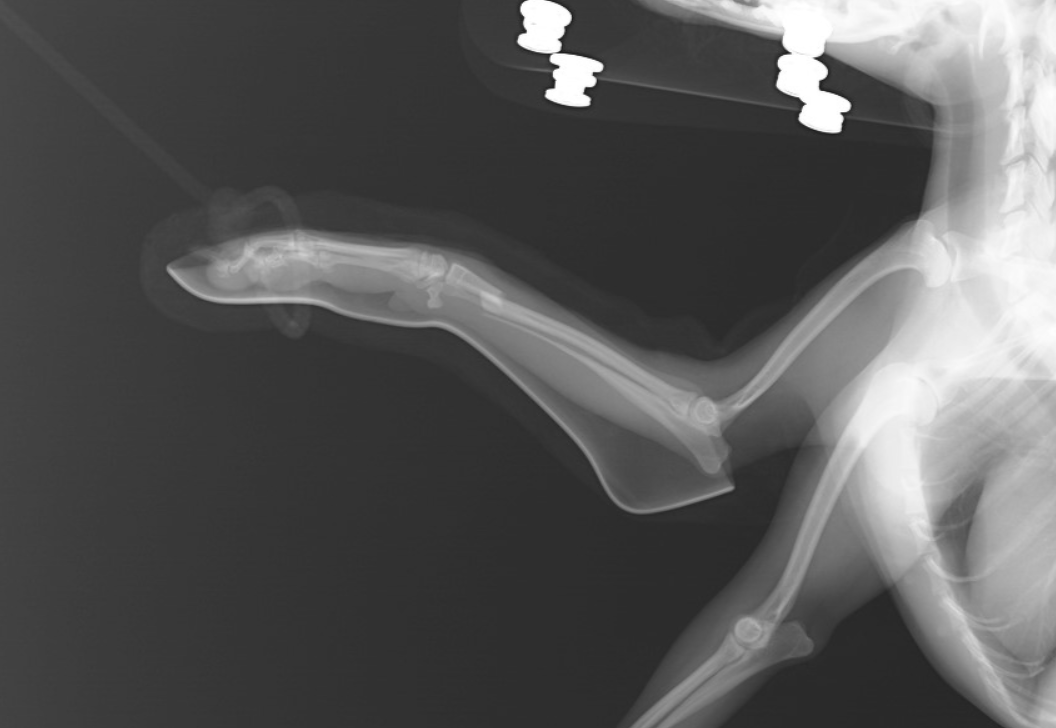

1. 外科手術: 骨折が複雑でずれている場合、外科手術が必要なことがあります。手術により骨を正しい位置に戻し、内部固定(金属プレートやピンで骨を固定)を行います。